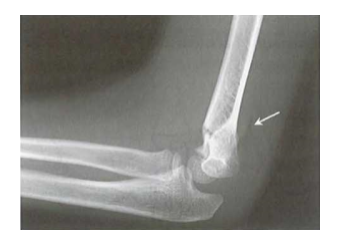

Loại I: gãy không di lệch hoặc di lệch tối thiểu (< 2 mm). Đôi khi trên phim XQ tổn thương xương khó xác định và dấu hiệu mỡ phía sau (Posterior fat pad sign) là dấu hiệu duy nhất chứng tỏ có tổn thương xương. Đây là dạng gãy vững.

Dấu hiệu mỡ phía sau trong gãy trên lồi cầu xương cánh tay Gartland I